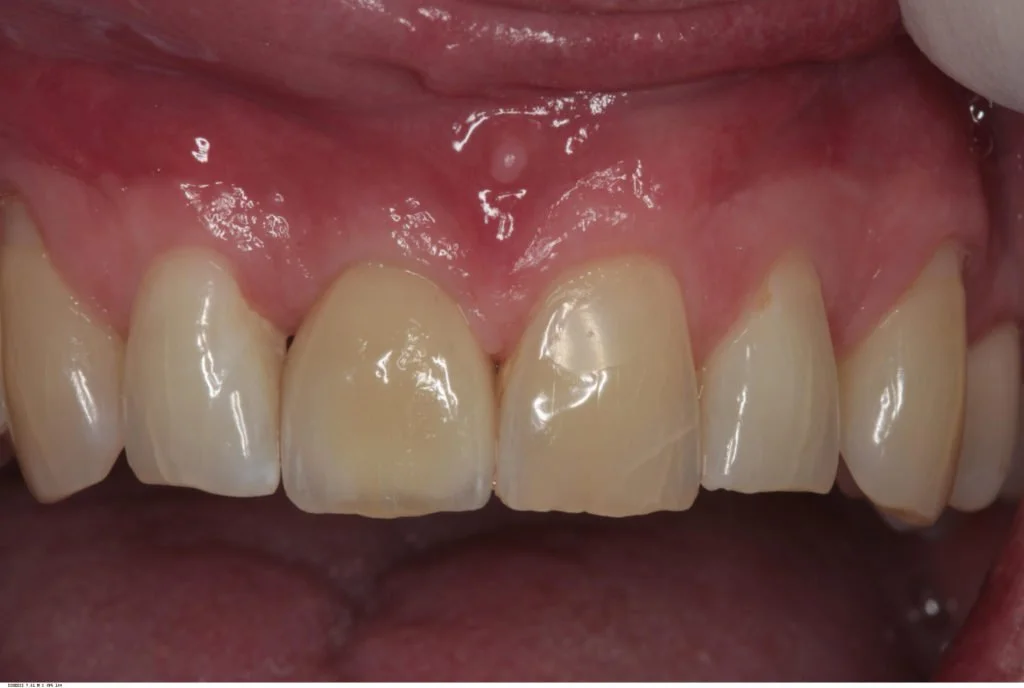

Following a four month post-operative review and confirmation of integration, this implant was then restored with a screw retained integrated abutment / veneered zirconia crown. The crown was then inserted and abutment screw torqued to 35 Ncm. The access cavity was restored with PTFe tape and composite resin. The occlusion was adjusted to ensure light Shim stock hold in ICP, and smooth concave protrusive guidance shared with the neighbouring central incisor.

Reviews carried out at both one year and then six years post operative, showed stable gingival symmetry, and the radiographs showed excellent bone level maintenance.